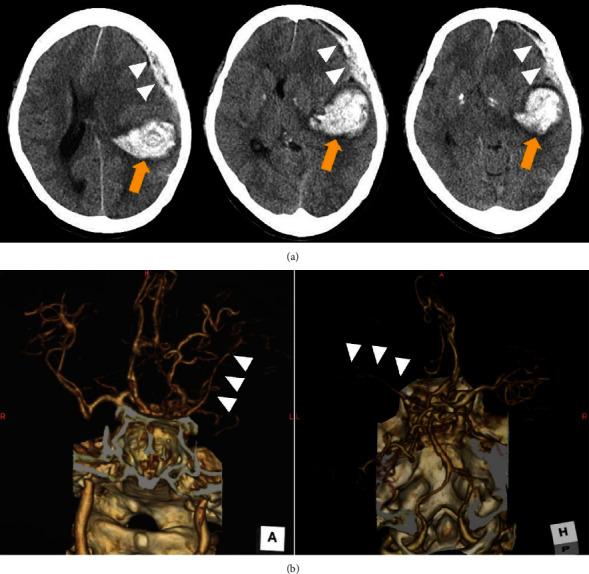

Moyamoya disease is often diagnosed after intracranial hemorrhage in adult patients. Here, we report a case of unilateral moyamoya disease treated with indirect revascularization combined with cranioplasty after treatment for acute subdural hematoma and subcortical hemorrhage. A middle-aged woman with disturbed consciousness was transferred to our hospital. Computed tomography (CT) revealed an acute subdural hematoma with left temporoparietal subcortical hemorrhage. Three-dimensional CT angiography indicated a scarcely enhanced left middle cerebral artery (MCA) that was suspected to be delayed or nonfilling due to increased intracranial pressure. Subsequently, hematoma evacuation and external decompression were performed. Postoperative digital subtraction angiography (DSA) revealed stenosis of the left MCA and moyamoya vessels, indicating unilateral moyamoya disease. Forty-five days after the initial procedure, we performed encephalo-arterio-synangiosis (EAS) using the superficial temporal artery simultaneously with cranioplasty for the skull defect. The modified Rankin Scale score of the patient one year after discharge was 1, and the repeat DSA showed good patency of the EAS. Revascularization using EAS in the second step can be an option for revascularization for hemorrhagic moyamoya disease if the patient required cranioplasty for postoperative skull defect after decompressive craniotomy.

摘要

烟雾病在成年患者中常于颅内出血后被诊断出来。在此,我们报告一例单侧烟雾病患者,在接受急性硬膜下血肿和皮质下出血治疗后,采用间接血管重建术联合颅骨成形术进行治疗。一名意识障碍的中年女性被转诊至我院。计算机断层扫描(CT)显示急性硬膜下血肿伴左侧颞顶叶皮质下出血。三维CT血管造影显示左侧大脑中动脉(MCA)强化极少,怀疑因颅内压升高导致延迟或未显影。随后,进行了血肿清除和外减压术。术后数字减影血管造影(DSA)显示左侧MCA狭窄及烟雾血管,提示单侧烟雾病。初次手术后45天,我们在颅骨缺损修补术的同时,使用颞浅动脉进行了脑动脉吻合术(EAS)。患者出院一年后的改良Rankin量表评分为1分,复查DSA显示EAS通畅良好。如果患者在减压性开颅术后因颅骨缺损需要进行颅骨成形术,第二步采用EAS进行血管重建可作为出血性烟雾病血管重建的一种选择。